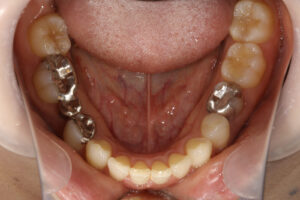

ラミネートベニア・セラミックインレー・アンレー・クラウン

内: セラミックインレー1本/80,000円、 セラミックアンレー80,000円、

ラミネートベニア1本120.000円

クリーニングの後、上顎前歯2本のラミネートベニア、右下臼歯部にセラミックブリッジを装着した。